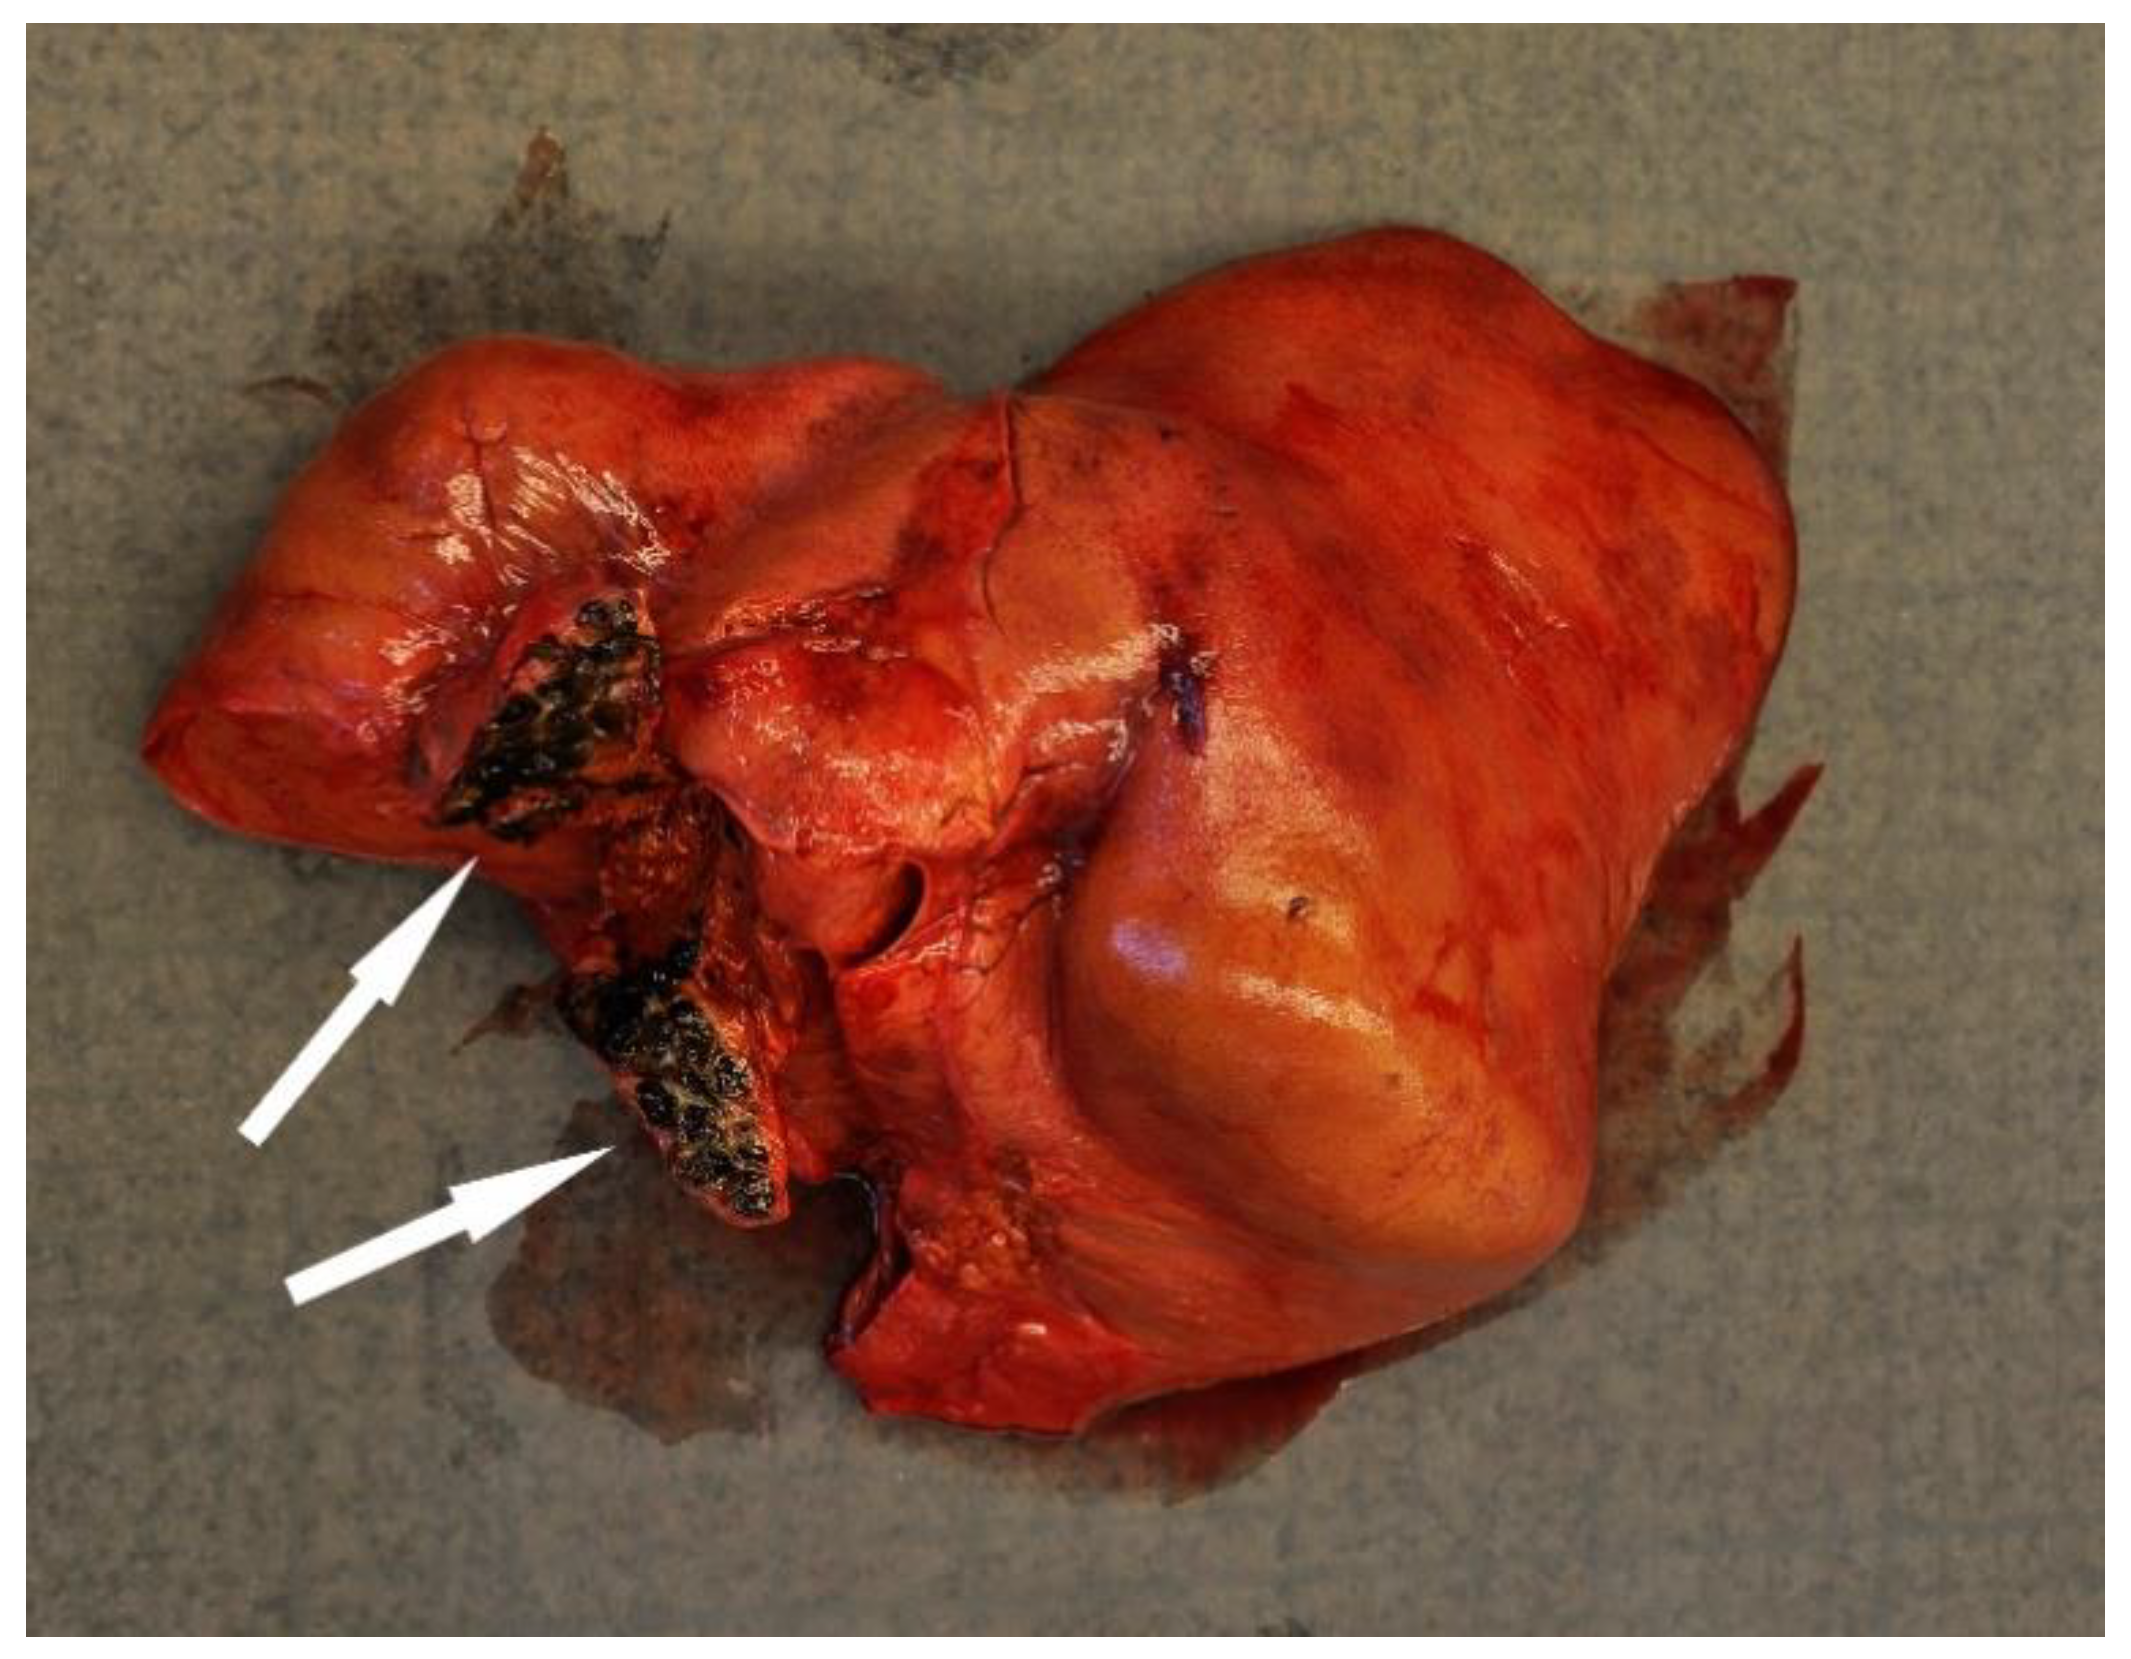

4.2.4. Trauma